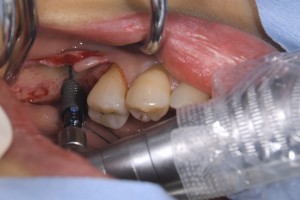

左下の6番部位にストローマンSLActiveロキソリッド4.1Φ12mmを埋入しました。

術前のCTで皮質骨が厚いものの海綿骨はClass Ⅳで柔らかいのがわかります。

両側の皮質骨で固定してなるべく長いインプラントを使用します。

使用した、ストローマンボーンレベルインプラントSLActiveロキソリッド RC4,1Φ12mmです。